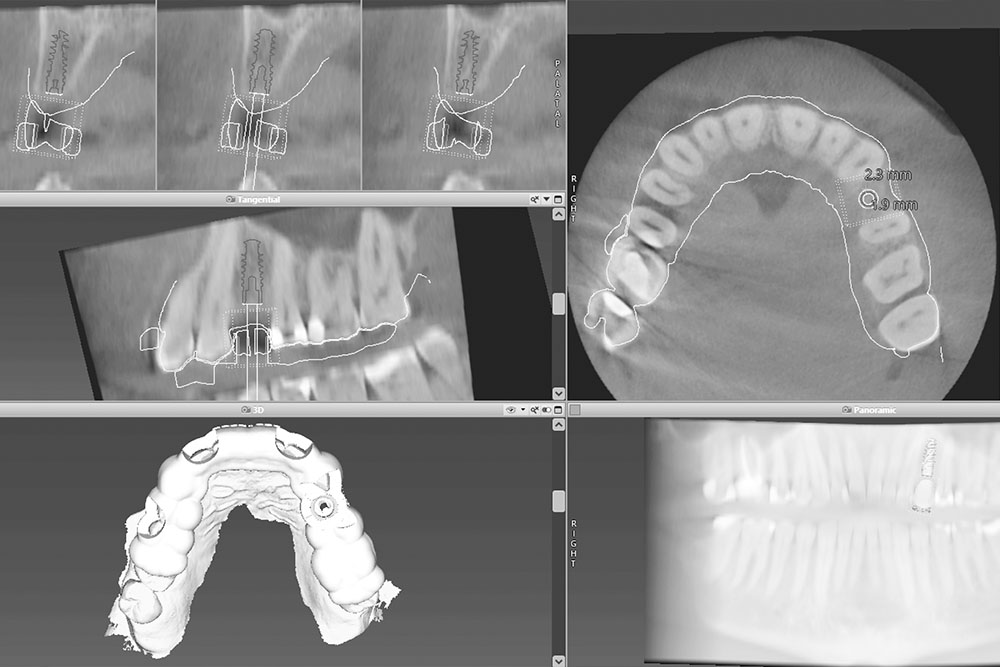

Unsere hochmoderne Ausstattung ermöglicht präzise 3D-geführte Implantationen, die maximale Sicherheit für die Einheilung von Zahnimplantaten bieten. Dank computergenerierter 3D-Bohrschablonen erfolgt die Implantation äußerst präzise und auf den Bruchteil eines Millimeters genau. Dieses innovative Verfahren legt den Grundstein für dauerhafte Stabilität Ihrer Implantate.

• 3D-gesteuerte & computergestützte Implantationstechniken

• DVT (3D-Röntgen)